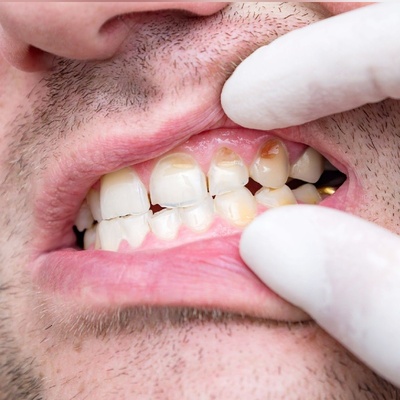

4 مشکل جدی و تغییر دندان با افزایش سن

تغییراتی که دراثر افزایش سن در دندان ها رخ می دهد؟